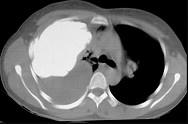

问题 男,66岁,剧烈胸痛,请结合CT图像,选择最可能的诊断 ( )

选项 A.右侧胸腔积液胸膜钙化 B.右肺癌侵犯胸膜 C.右侧胸膜间皮瘤 D.右侧肺不张 E.右侧肺肺癌

答案 C